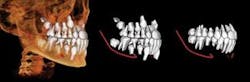

Dolphin Imaging® (dolphinimaging.com) and InVivoDental by Anatomage® (www.anatomage.com) are two software developers who are on the cutting edge of software for orthodontic and orthognathic treatment-planning and archiving. Both packages offer conventional cephalometric analysis based upon digitized 3-D volume renderings. The soft tissue and facial photos (in 2-D or stereographic formats via 3-D MD camera system) can be superimposed and phased in over the skeleton with a translucency feature. This feature enables integrated dento-facial analysis showing how the soft tissues are influenced by dento-skeletal positions. Location, size, and density of lesions and bone cysts — as well as positions impacted and supernumerary teeth — can be rendered in 2-D and 3-D to help determine the best approach for surgical access. (Figure 2).

CBCT images can be modeled by Anatomage in the traditional form of digital study casts. They can then be viewed and morphed into desired tooth positions. The pre/post treatment CBCT scans can be superimposed showing the positional change between the two, which is actually 4D imaging (Figure 3). An animated, digital morph movie can be made to show the before and after morphing.